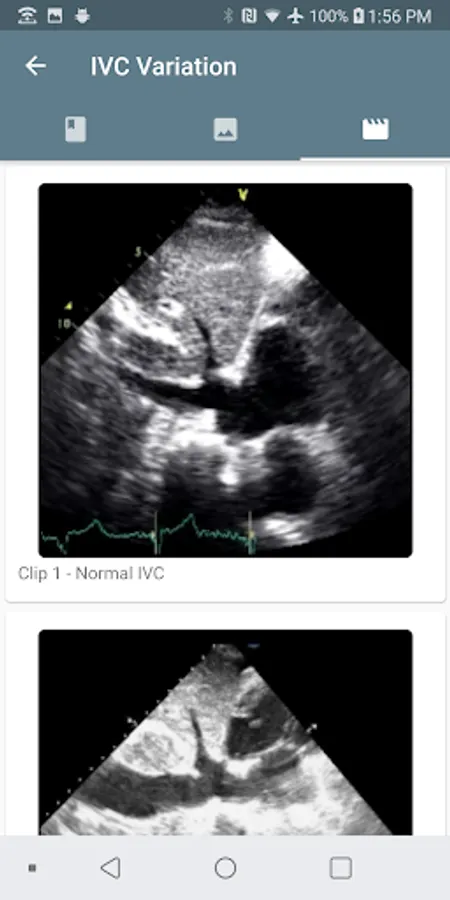

Use the calculators to get the cardiac output, stroke volume, systemic vascular resistance, inferior vena cava respiratory variation, and other metrics. The educational content can be accessed from the calculator so that the learning continues.